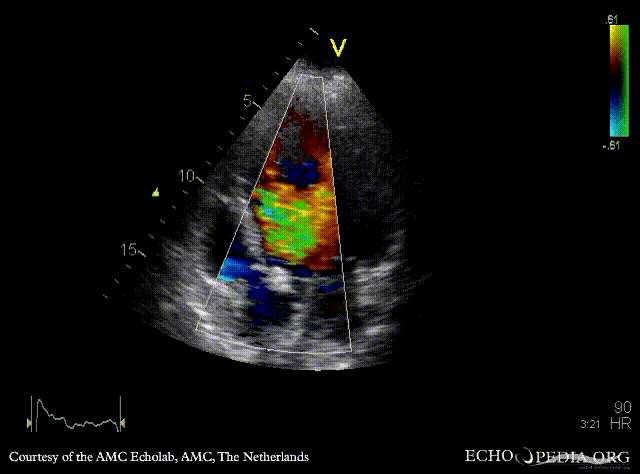

A4CH: Color Doppler, severe aortic regurgitation Continuous-wave doppler signal of severe aortic regurgitation